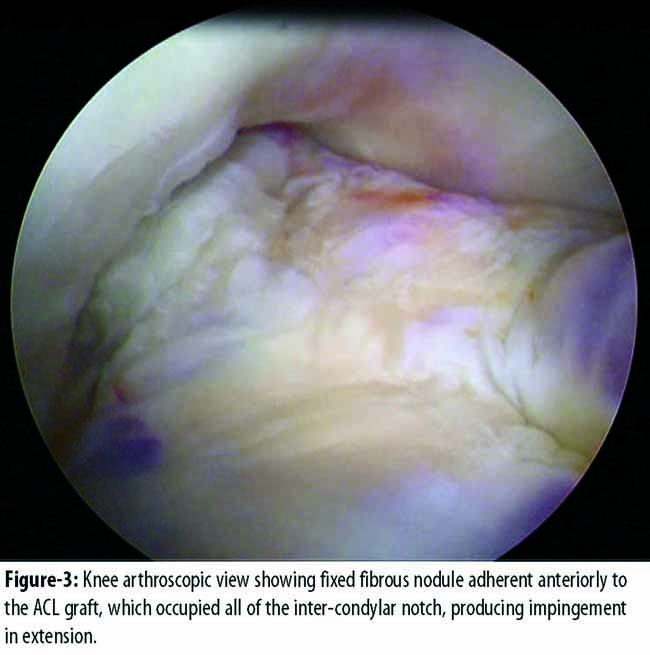

The patient underwent arthroscopy in May 2015, which revealed a fixed fibrous nodule adherent anteriorly to the ACL graft and impinging on the inter-condylar notch in extension (Figure-3)